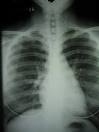

The most common type is termed serous membrane carcinoma that attacks the serosa or inner lining of the lungs. The amphibole fibers indrawn develop scars inflicting harm to the cells found within the inner lining. Symptoms tend to be an absence of breath, pains within the chest and retention of fluid within the lungs.

The Butman system may be a term accustomed describe completely different stages of a growth caused by carcinoma. the primary stage signifies a presence in either the correct or left aspect of the serosa, serosa or diaphragm. The second stage is wherever the growth has unfold to either side, the musculature, heart, chest wall or humour nodes. The third stage is wherever the cancer has unfold from the diaphragm into the serosa or abdomen lining and is understood because the serious assaulting part. Stage four indicates the growth has unfold to the opposite organs through the blood. CAT scans, magnetic resonance imaging testing and X-rays square measure accustomed confirm that stage a patient has reached. This data is important choose the sort of treatment that ought to be used.